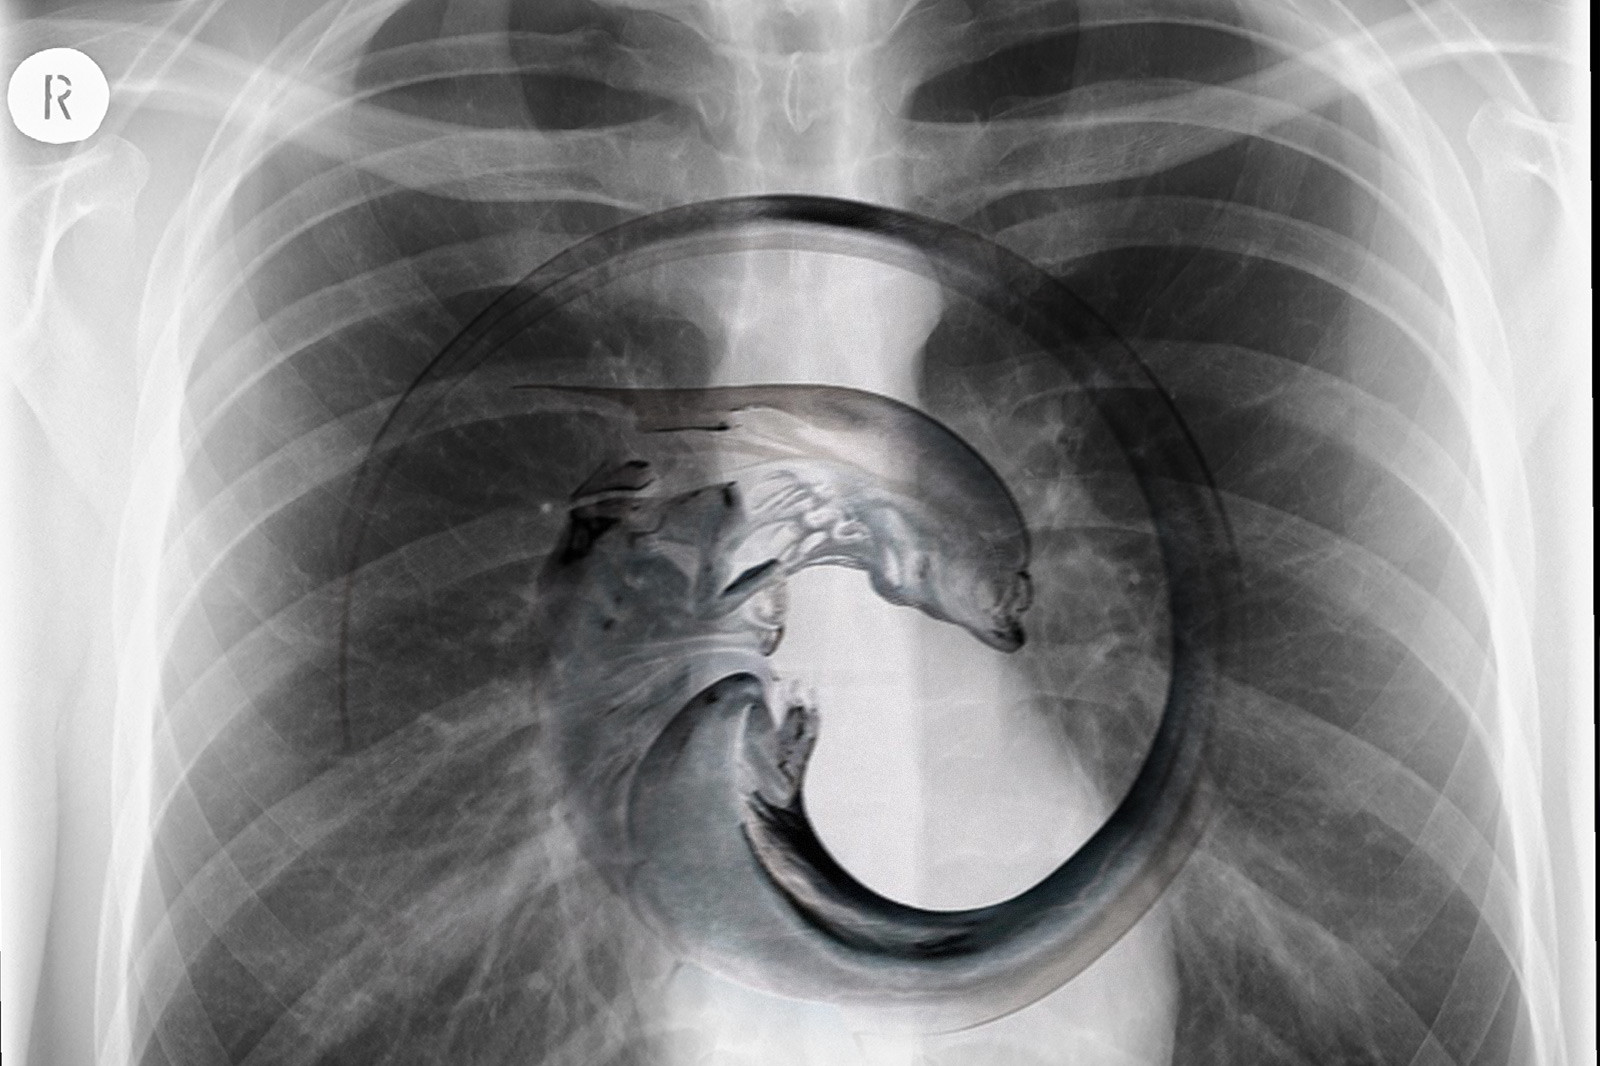

Необычные рентгеновские снимки: то, что скрыто внутри

Раздел: Визуальный дайджест